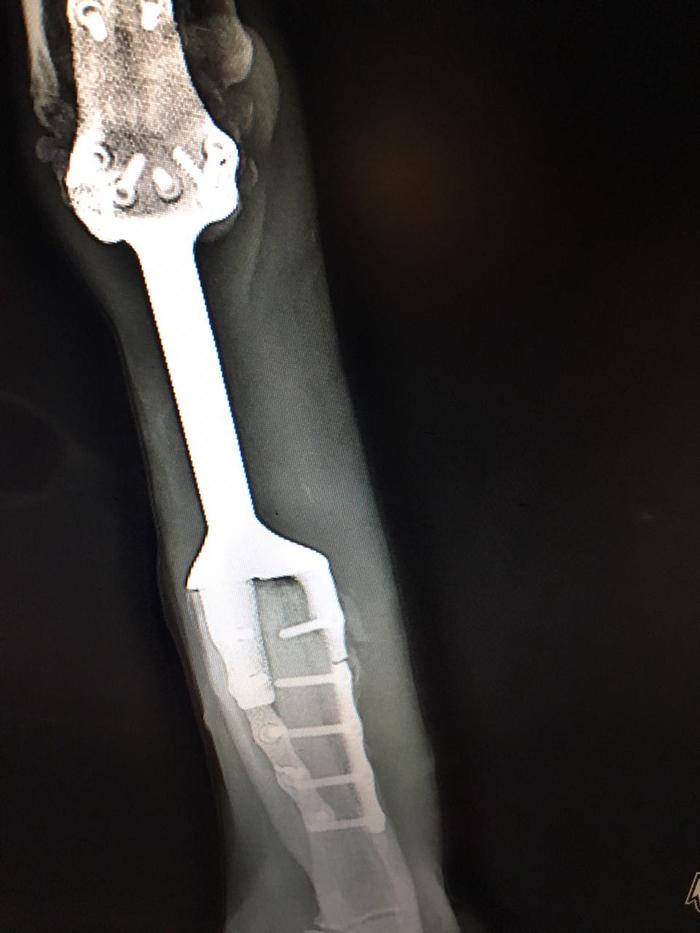

Через несколько дней ребята из организации, где печатали первый протез, напечатали ему пластиковую штуку (я фиг знает как это назвать правильно), которая прикручивалась к остатку титановой ноги. Тут от меня им безмерная благодарность, т.к. мало того, что не взяли ни копейки, так еще и отношение у них к работе выше всяких похвал. Забегая вперед, мы у них еще не раз были, таких болеющих за работу еще поискать. Кому интересно, обязательно все названия напишу.

На этой ноге он приспособился ходить очень быстро, даже бегал слегка, я правда не давала ему воли, мне до сих пор страшно что сломается эта палка титановая или кость, в которой она закреплена.